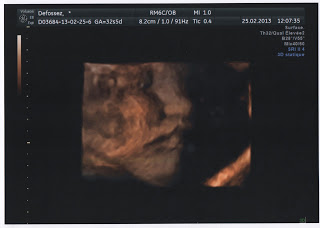

Maxine a 7 mois! (enfin… -2 mois)

Pour le jour de son moisiversaire négatif (bah oui elle a -2 mois :p), nous avons eu le droit de voir Maxine lors de l’échographie du troisième trimestre. L’occasion pour nous de faire un beau cadeau d’anniversaire à ma maman qui n’a toujours pas eu l’occasion de sentir bouger sa petite fille (elle est timide…

Par Céline 25 février 2013 0